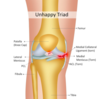

What is the unhappy triad?

- Three tears due to a strong force applied to the lateral aspect of the knee

- Medial meniscus is adherent to medial collateral ligament which is why it tears too

What collateral ligament breaks with each strain?

- Valgus: medial at risk (more common)

- Varus: lateral at risk

- LCL break will cause more knee instability as shallower socket for femoral condyle on lateral side